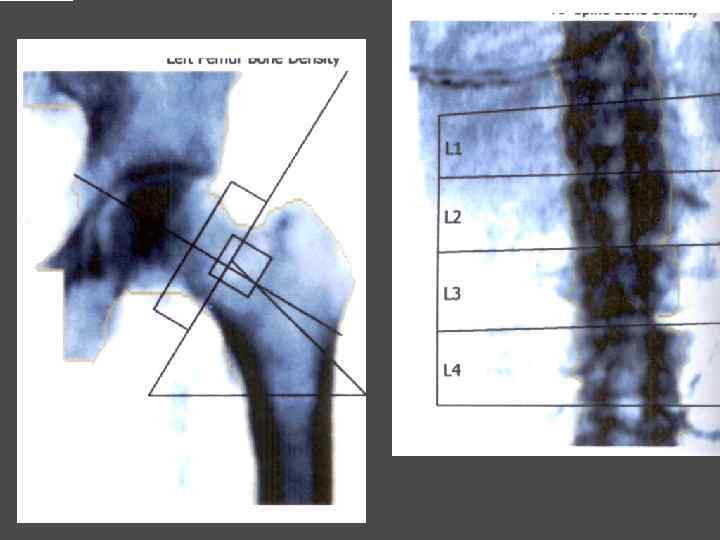

МЕТОДЫ ИССЛЕДОВАНИЯ ► Определения уровня кальция крови, паратгормона ► Сцинтиграфия паращитовидных желез с Тс99 ► УЗИ ► ПТАБ ► КТ, МРТ ► Денситометрия